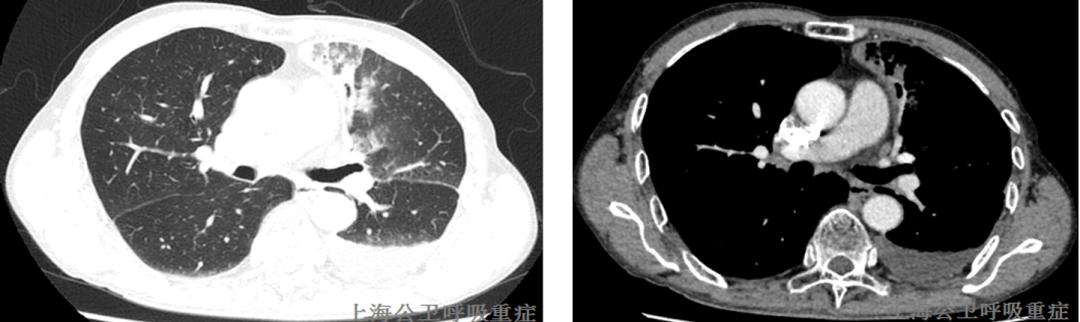

2020.11.30复查胸部CT示:左肺上叶尖后段、左肺下叶外基底段及前内基底段实性结节;左肺少许炎症;左侧少量胸腔积液;左侧胸膜增厚;较前2020-11-26片,左肺下叶前内基底段病灶略减小,左肺下叶外基底段新发实性结节,左侧胸腔积液略增多,左肺上叶尖后段病灶相仿。左肺门淋巴结肿大,与前片相仿;两上肺胸膜下小肺大泡。气管右后方增厚软组织影,建议颈部MRI增强检查。

2020.12.01颈部CT增强示:右侧喉部软组织占位,两侧颈部多发肿大淋巴结,部分融合——考虑MT伴颈部淋巴结转移可能大,请进一步检查。